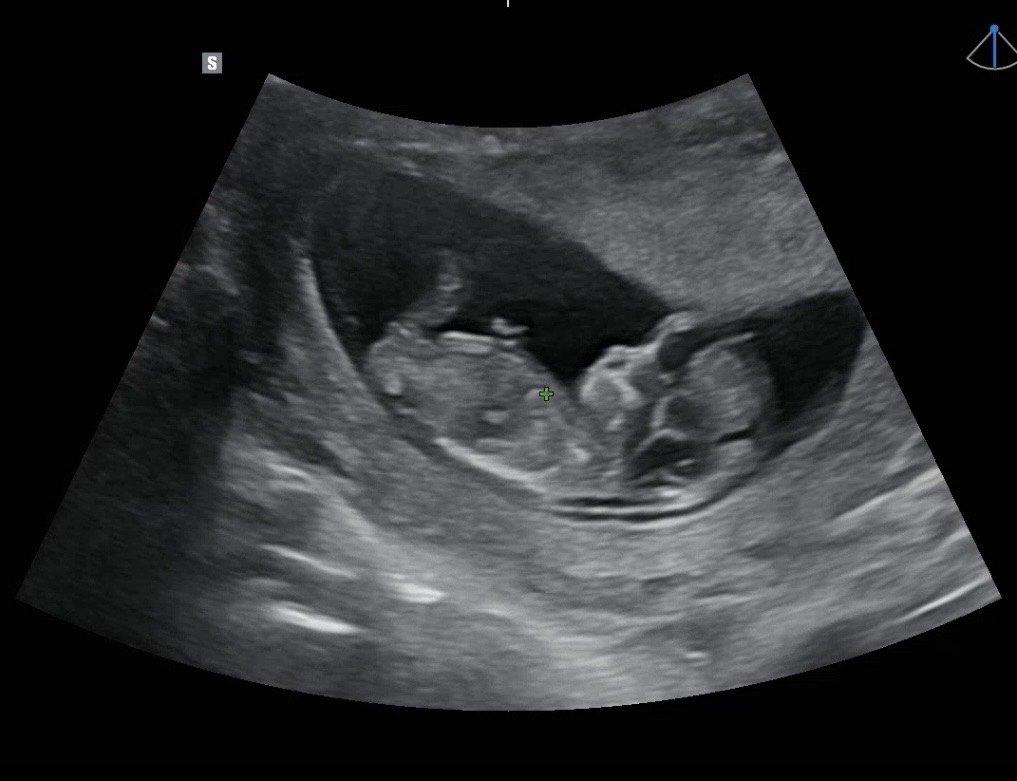

12주 0일 각도법 봐주세요오🫶🏻

각도가 애매한데… 남자일까요 여자일까요😳 좋은 하루 되세요🫶🏻🫶🏻